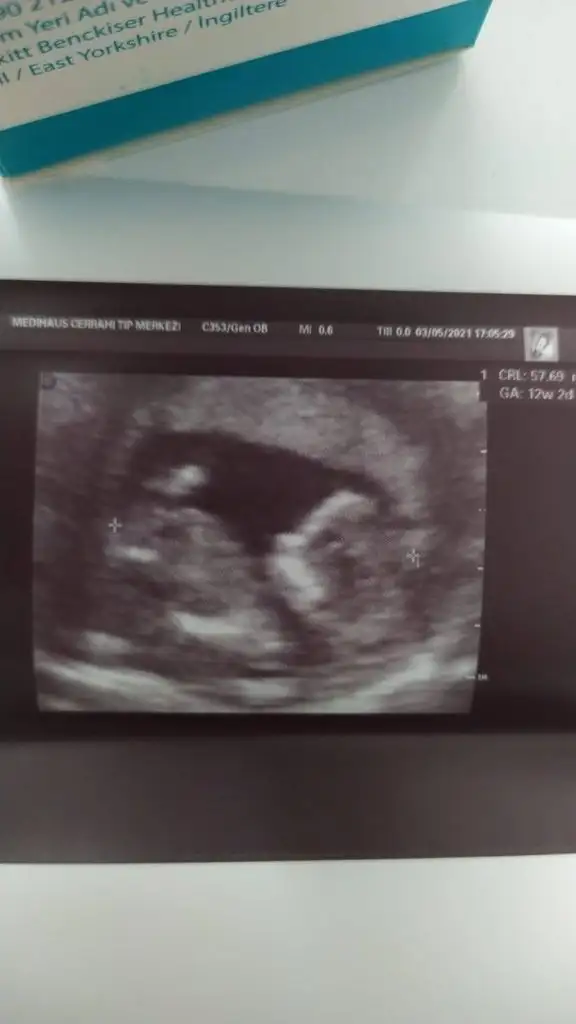

Bana da bakar misiniz ilki 6+4 vajinal diger ikisi 12+5 karindan cinsiyet belli degil henuz tahmin ederseniz sevinirim